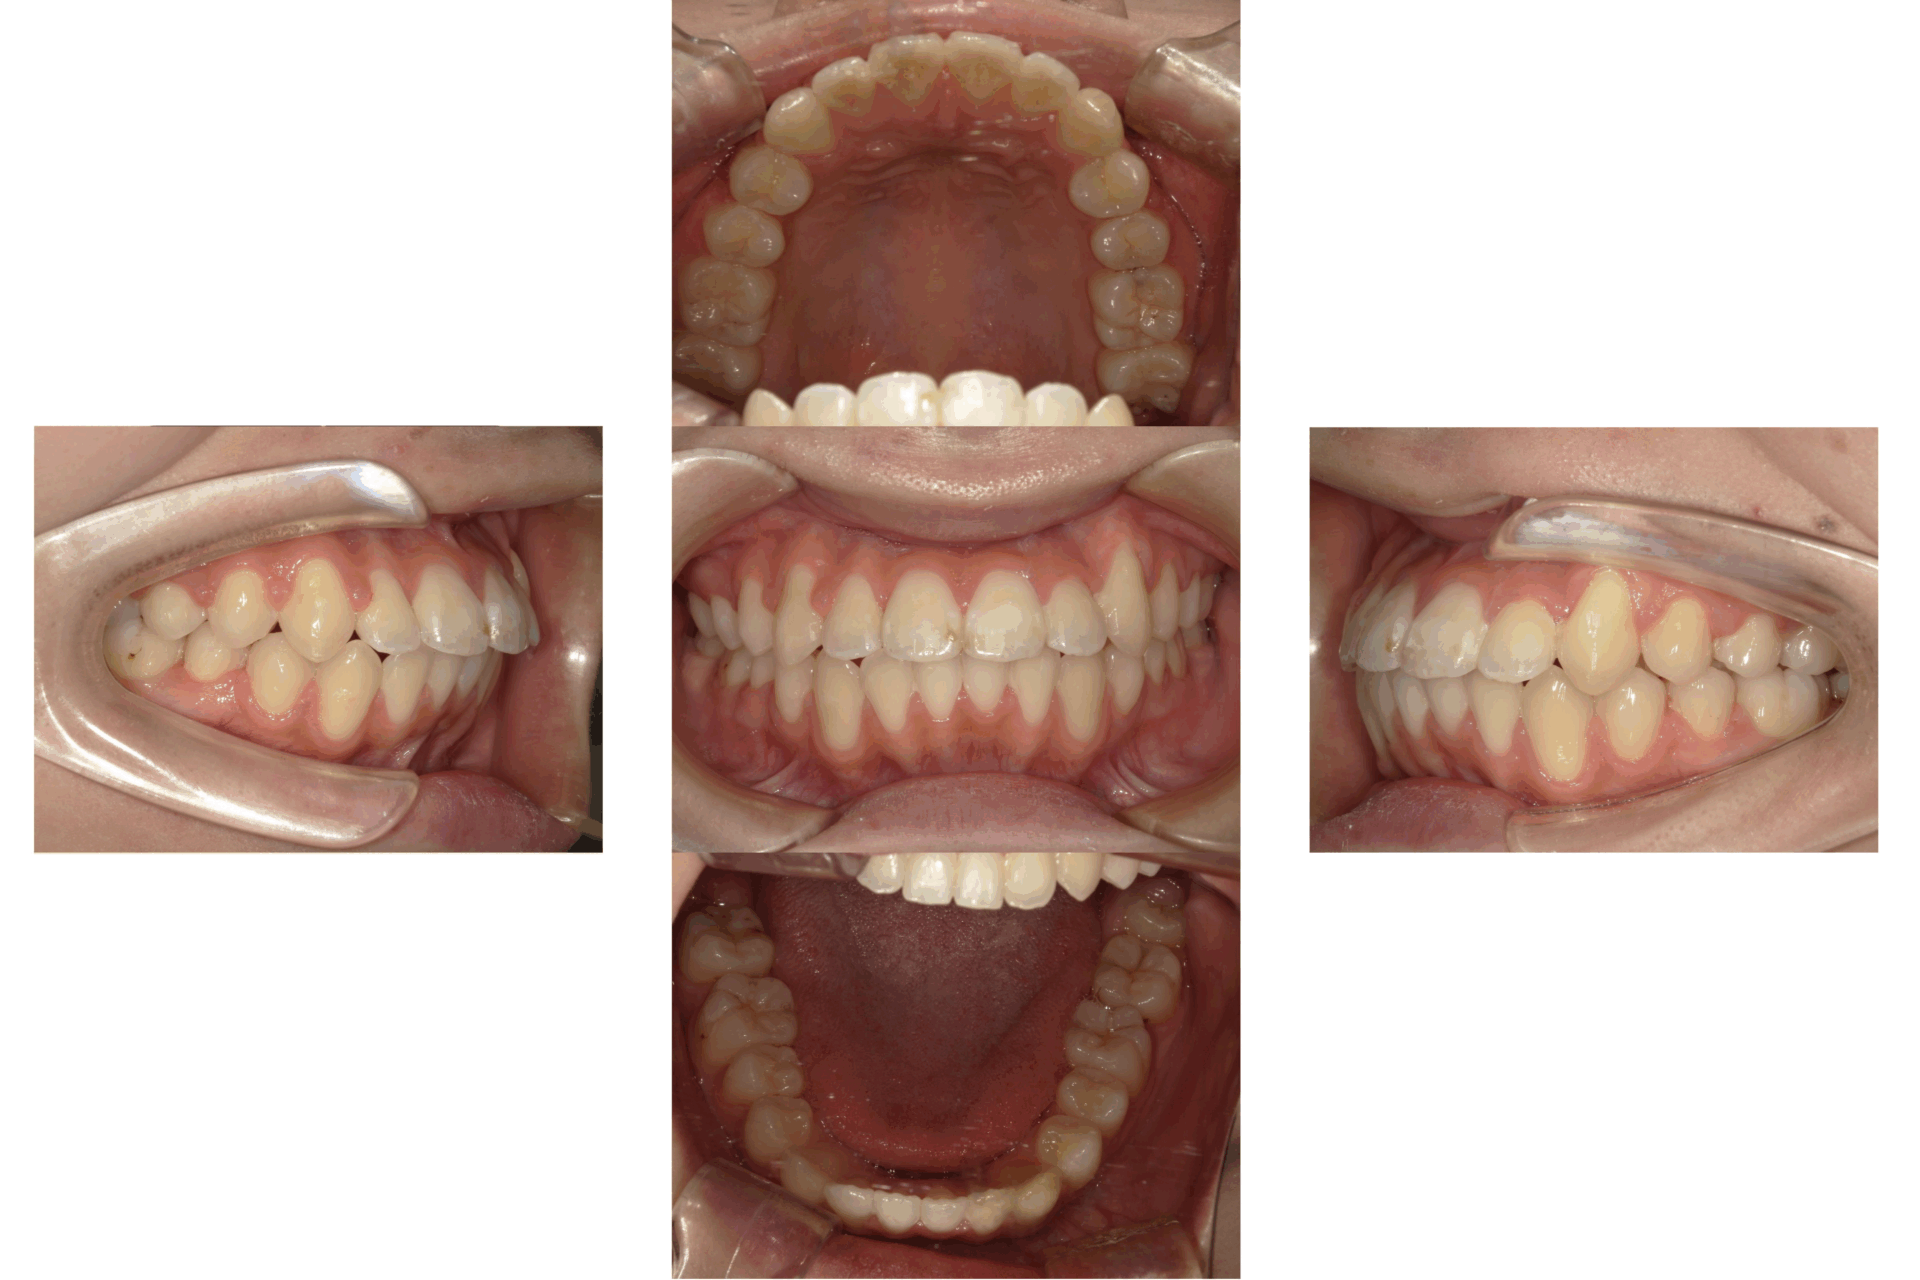

20代、女性、ワイヤー

| 施術内容 | 主訴:全体的に凸凹が気になる 詳細:ワイヤー矯正での歯並び改善 ずっと磨きにくく、臭いが気になっていましたが、 矯正後は磨きやすくなり、臭いも無くなって満足された症例です。 |

| 治療期間 | 16ヶ月(3/13現在 治療終了) |

| 費用 | ワイヤー矯正 60万円(税込660,000円) |